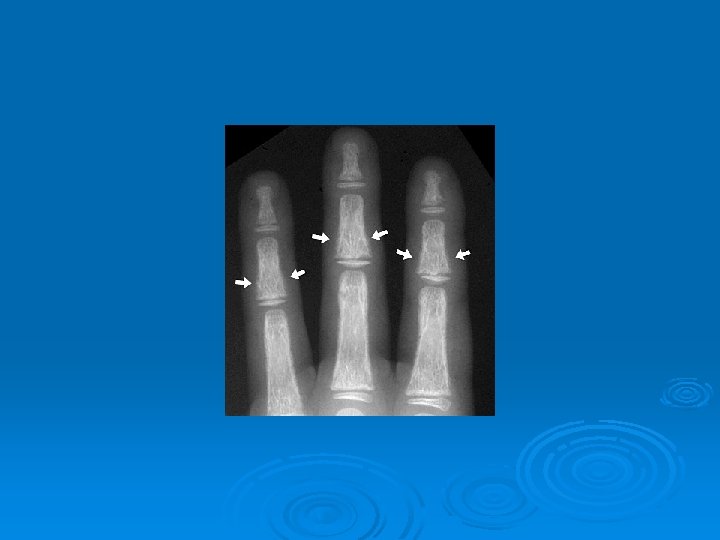

Symptoms of hyperparathyroidism Ø "Bones, stones, abdominal groans, and psychic moans ". Ø Skeletal manifestations-- ---pseudogout, and chondrocalcinosis , osteitis fibrosa cystica, causing subperiosteal resorption, and the skull causing the radiologic appearance known as salt and pepper skull. Ø Renal manifestations ---polyuria, kidney stones, hypercalciuria, and rarely nephrocalcinosis.

Imaging Studies Ø Ultrasonography and 99 m. Tc sestamibi scanning have the advantages of being widely available and relatively inexpensive compared but is operator-dependent. Ø Radiology ---- subperiosteal resorption at the radial sides of the phalanges, distal phalangeal tufts, and distal clavicles. Ø Skull Xray ---- pepar salt apperance . Ø (DXA) at the hip and spine ---- ostoprosis.